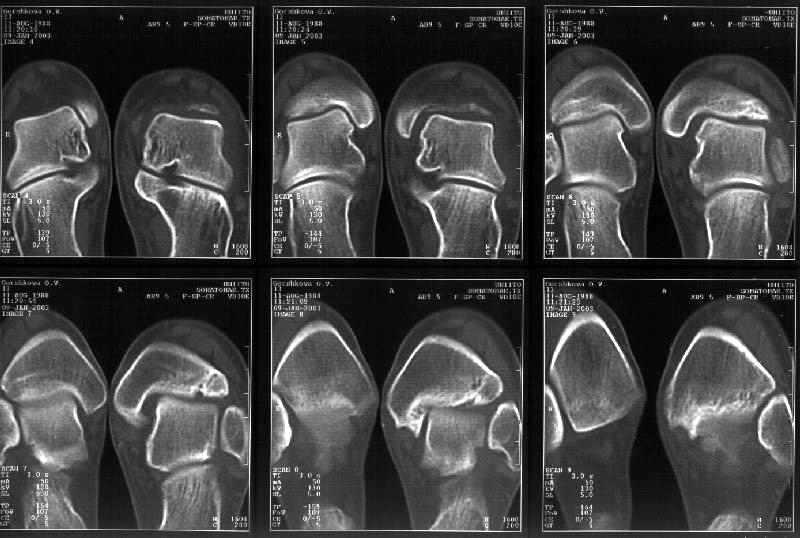

На следующий день пациентке сделали КТ. Может быть, после просмотра картинки будут другие предложения? Не убрать ли ве-таки этот фрагмент

позади внутренней лодыжки, который оттесняет таран кнаружи?

Думаю, КТ прочитан не верно. Задняя часть медиального маллеола, в сущности уже часть заднего маллеола стоит на месте и трогать её не следует. Передняя часть маллеола на 3-4 мм удалена от тарана. Сравните с пространством между

латеральным маллеолом и тараном. В норме все три должны быть одинаковы: между тараном и латеральным, задним и медиальным. Это главное условие устойчивого сидения тарана в голеностопном суставе.

Все-таки она как раз была была отколота и вместе с тараном смещена латерально.

Внутренняя лодыжка не была сломана, она как была на своем месте, так там и находится. Это таран от нее отдавлен кнаружи смщенным в его сторону фрагментом позади внутренней лодыжки. За счет чего и есть проявления нестабильности связок.

Вот и проблема. Восстанавливать ли эту равномерность сейчас, и если да, то как. Вот точка зрения коллеги из Штатов:

Здесь 4 среза, начиная от основания лодыжки и проксимальнее. Где, по Вашему мнению, проходит линия перелома, отделяющая переднюю часть внутренней лодыжки от большеберцовой кости? Заранее спасибо.

Я пометил линию перелома черной линией.

К сожалению на последних присланных срезах КТ нет более низкого, через таран, среза, который был на прежнем майле. На XR я попытался показать

стержень внутри сустава и то как он раскрывает пространство между тараном и мед. малеолом.

На КТ я попытался изобразить скромными своими способностями (А)- место перелома, (С)- нормальный суставной зазор меж тараном и тремя его маллеолами. (В)- образовавшийся в результате перелома широкий раза в три зазор, позволяющий, по-моему, сублюксацию тарана при ходьбе. В свете данных КТ, критически важных, я бы предложил вертикальную остеотомию места перелома

задне-внутренним подходом и фиксацию мед. маллеола прижатым к тарану с помощью тонкого compression screw. После этого гипсовый сапожок и немедленное расхаживание ноги.